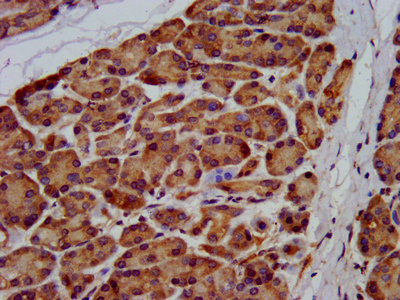

IHC image of CSB-PA890777LA01HU diluted at 1:200 and staining in paraffin-embedded human pancreatic tissue performed on a Leica BondTM system. After dewaxing and hydration, antigen retrieval was mediated by high pressure in a citrate buffer (pH 6.0). Section was blocked with 10% normal goat serum 30min at RT. Then primary antibody (1% BSA) was incubated at 4°C overnight. The primary is detected by a biotinylated secondary antibody and visualized using an HRP conjugated SP system.